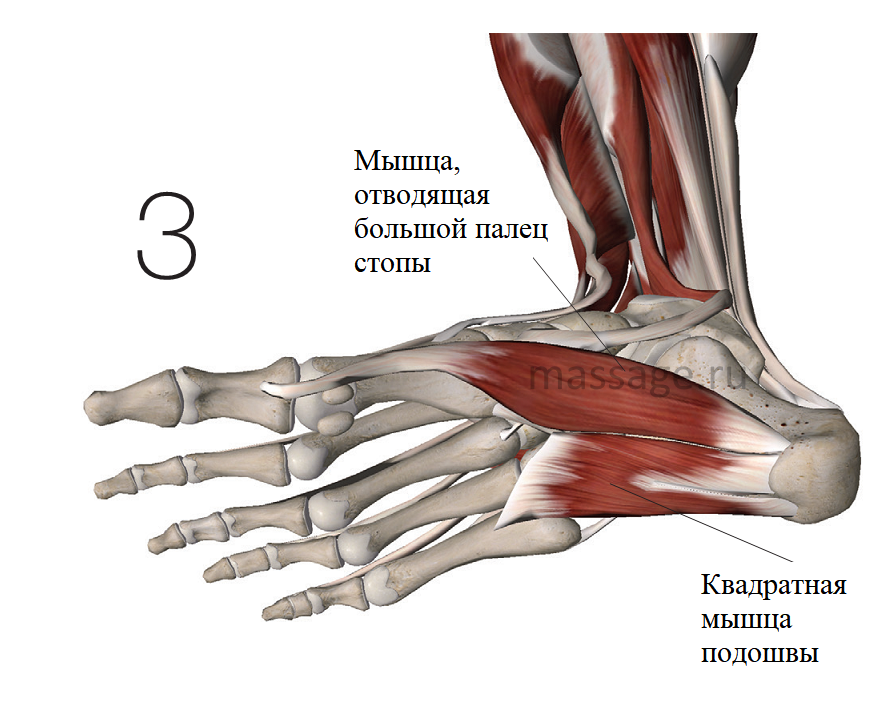

Анатомия подошвенной мышцы голени: подробное рассмотрение